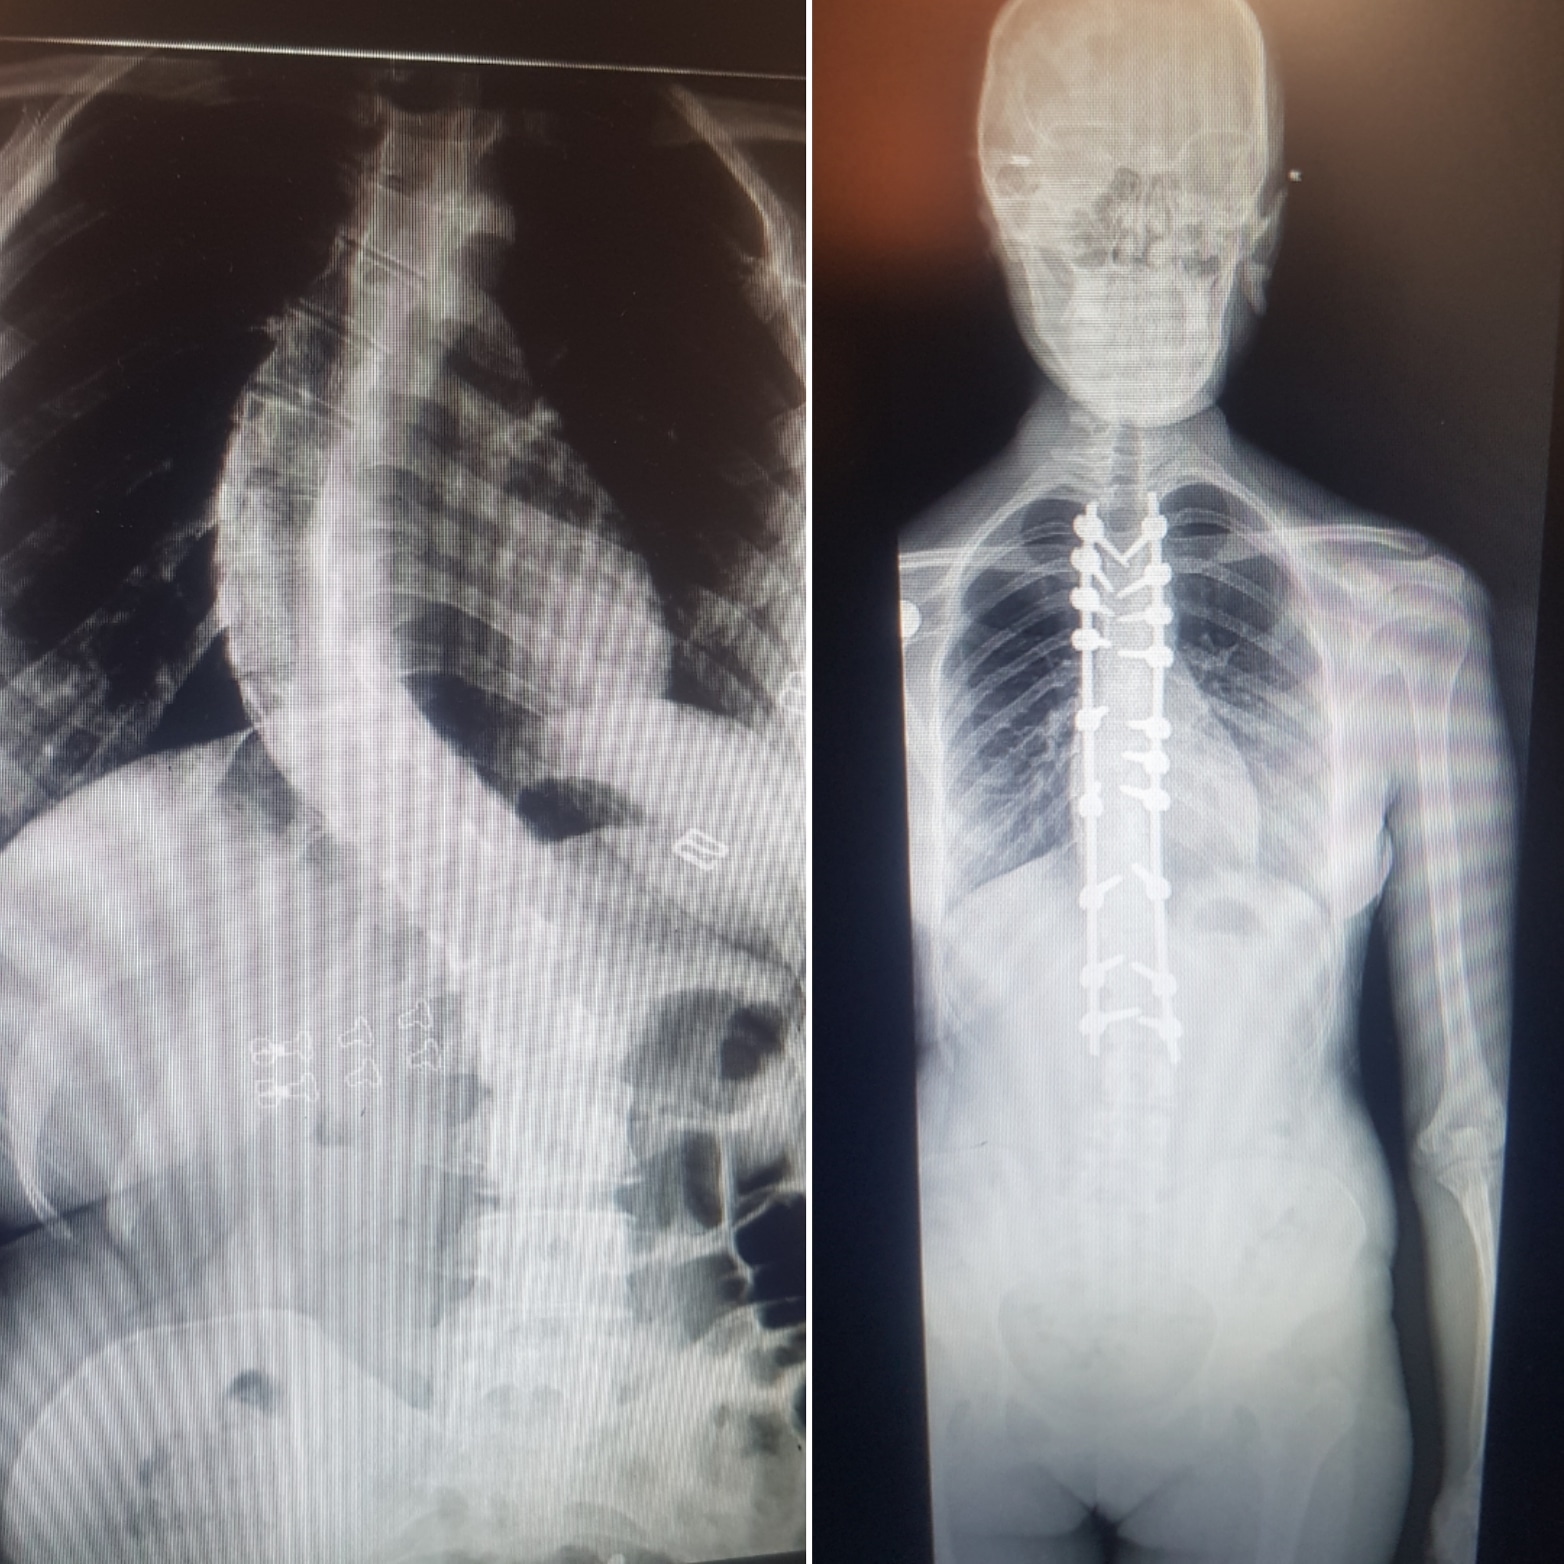

Skolyoz Hastalığı Serdar YÜKSEL